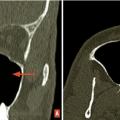

Rhinosinusites de l’enfant

La rhinosinusite se définit comme une inflammation de la muqueuse d’un ou plusieurs sinus de la face. Chez l’enfant, le terme de rhinosinusite remplace celui de sinusite car il est exceptionnel que l’atteinte de la muqueuse sinusienne soit isolée comme dans les sinusites dentaires ou précède l’atteinte du nez comme dans les…

Pathologie rhinosinusienne : les messages clés

1 La rhinosinusite aiguë de l’enfant ne relève habituellement que des soins locaux.2 L’ethmoïdite, avec son risque d’abcédation intra- orbitaire, reste la complication la plus sérieuse de la rhinosinusite de l’enfant. Elle justifie hospitalisation, antibiothérapie, surveillance rapprochée, voire drainage chirugical.3 La…